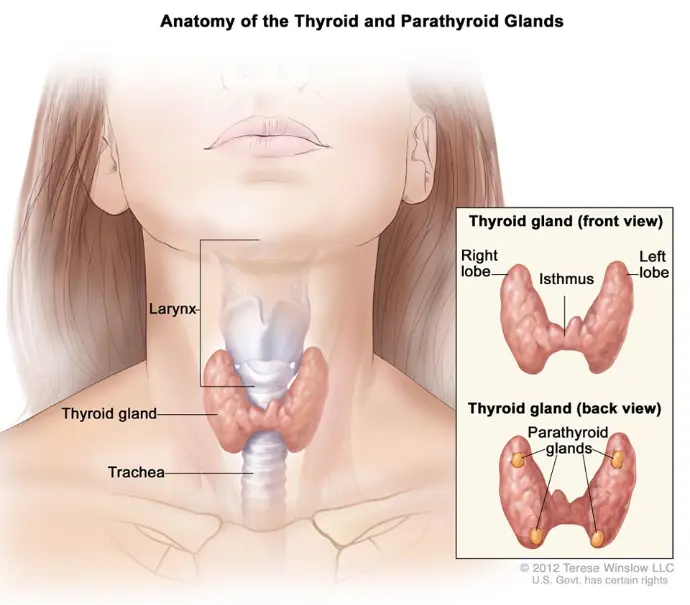

آلية عمل الغدة الدرقية

تعمل الغدة الدرقية تحت سيطرة محور الغدة النخامية والغدة تحت المهاد :

3. تضخم الغدة الدرقية (Goiter):

تضخم في حجم الغدة الدرقية.

4. العقد الدرقية (Thyroid Nodules):

تكون كتل صغيرة داخل الغدة الدرقية.